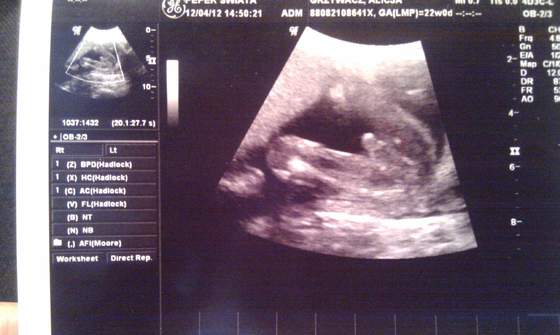

Dzidziuś pięknie wygląda, jest zdrowy, ruchliwy, ziewał sobie, pokazał pitoczka ze wszystkich stron (z tej okazji znów kupiłam dzisiaj kilka niebieskich ciuszków), nie wiem ile ma długości ale waży 310 gram, więc chyba do wielkoludów nie należy ale nie wiem bo się nie znam. Doktor mówił że wszystko jest ok, to znaczy że ok

oglądaliśmy wszystkie obszary mózgu, komory i przedsionki serca, oraz inne organy wewnętrzne. Najfajniej jednak wyglądały stópki :-)